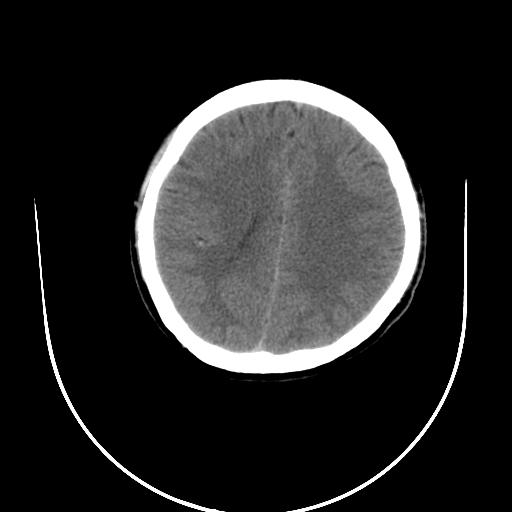

标题: CT10010:女/24岁,癫痫一周,发作时间不固定. [打印本页]

标题: CT10010:女/24岁,癫痫一周,发作时间不固定.

右侧额叶正常吗?

右额叶镰旁饱满.

右侧外侧沟?中央沟?可能有问题,不知以前有没有癫痫过,最好是增强下,排除局部血管畸形等病变

倒数第6幅图中线结构有点偏,而侧脑室额角未见异常,可结合增强扫描。